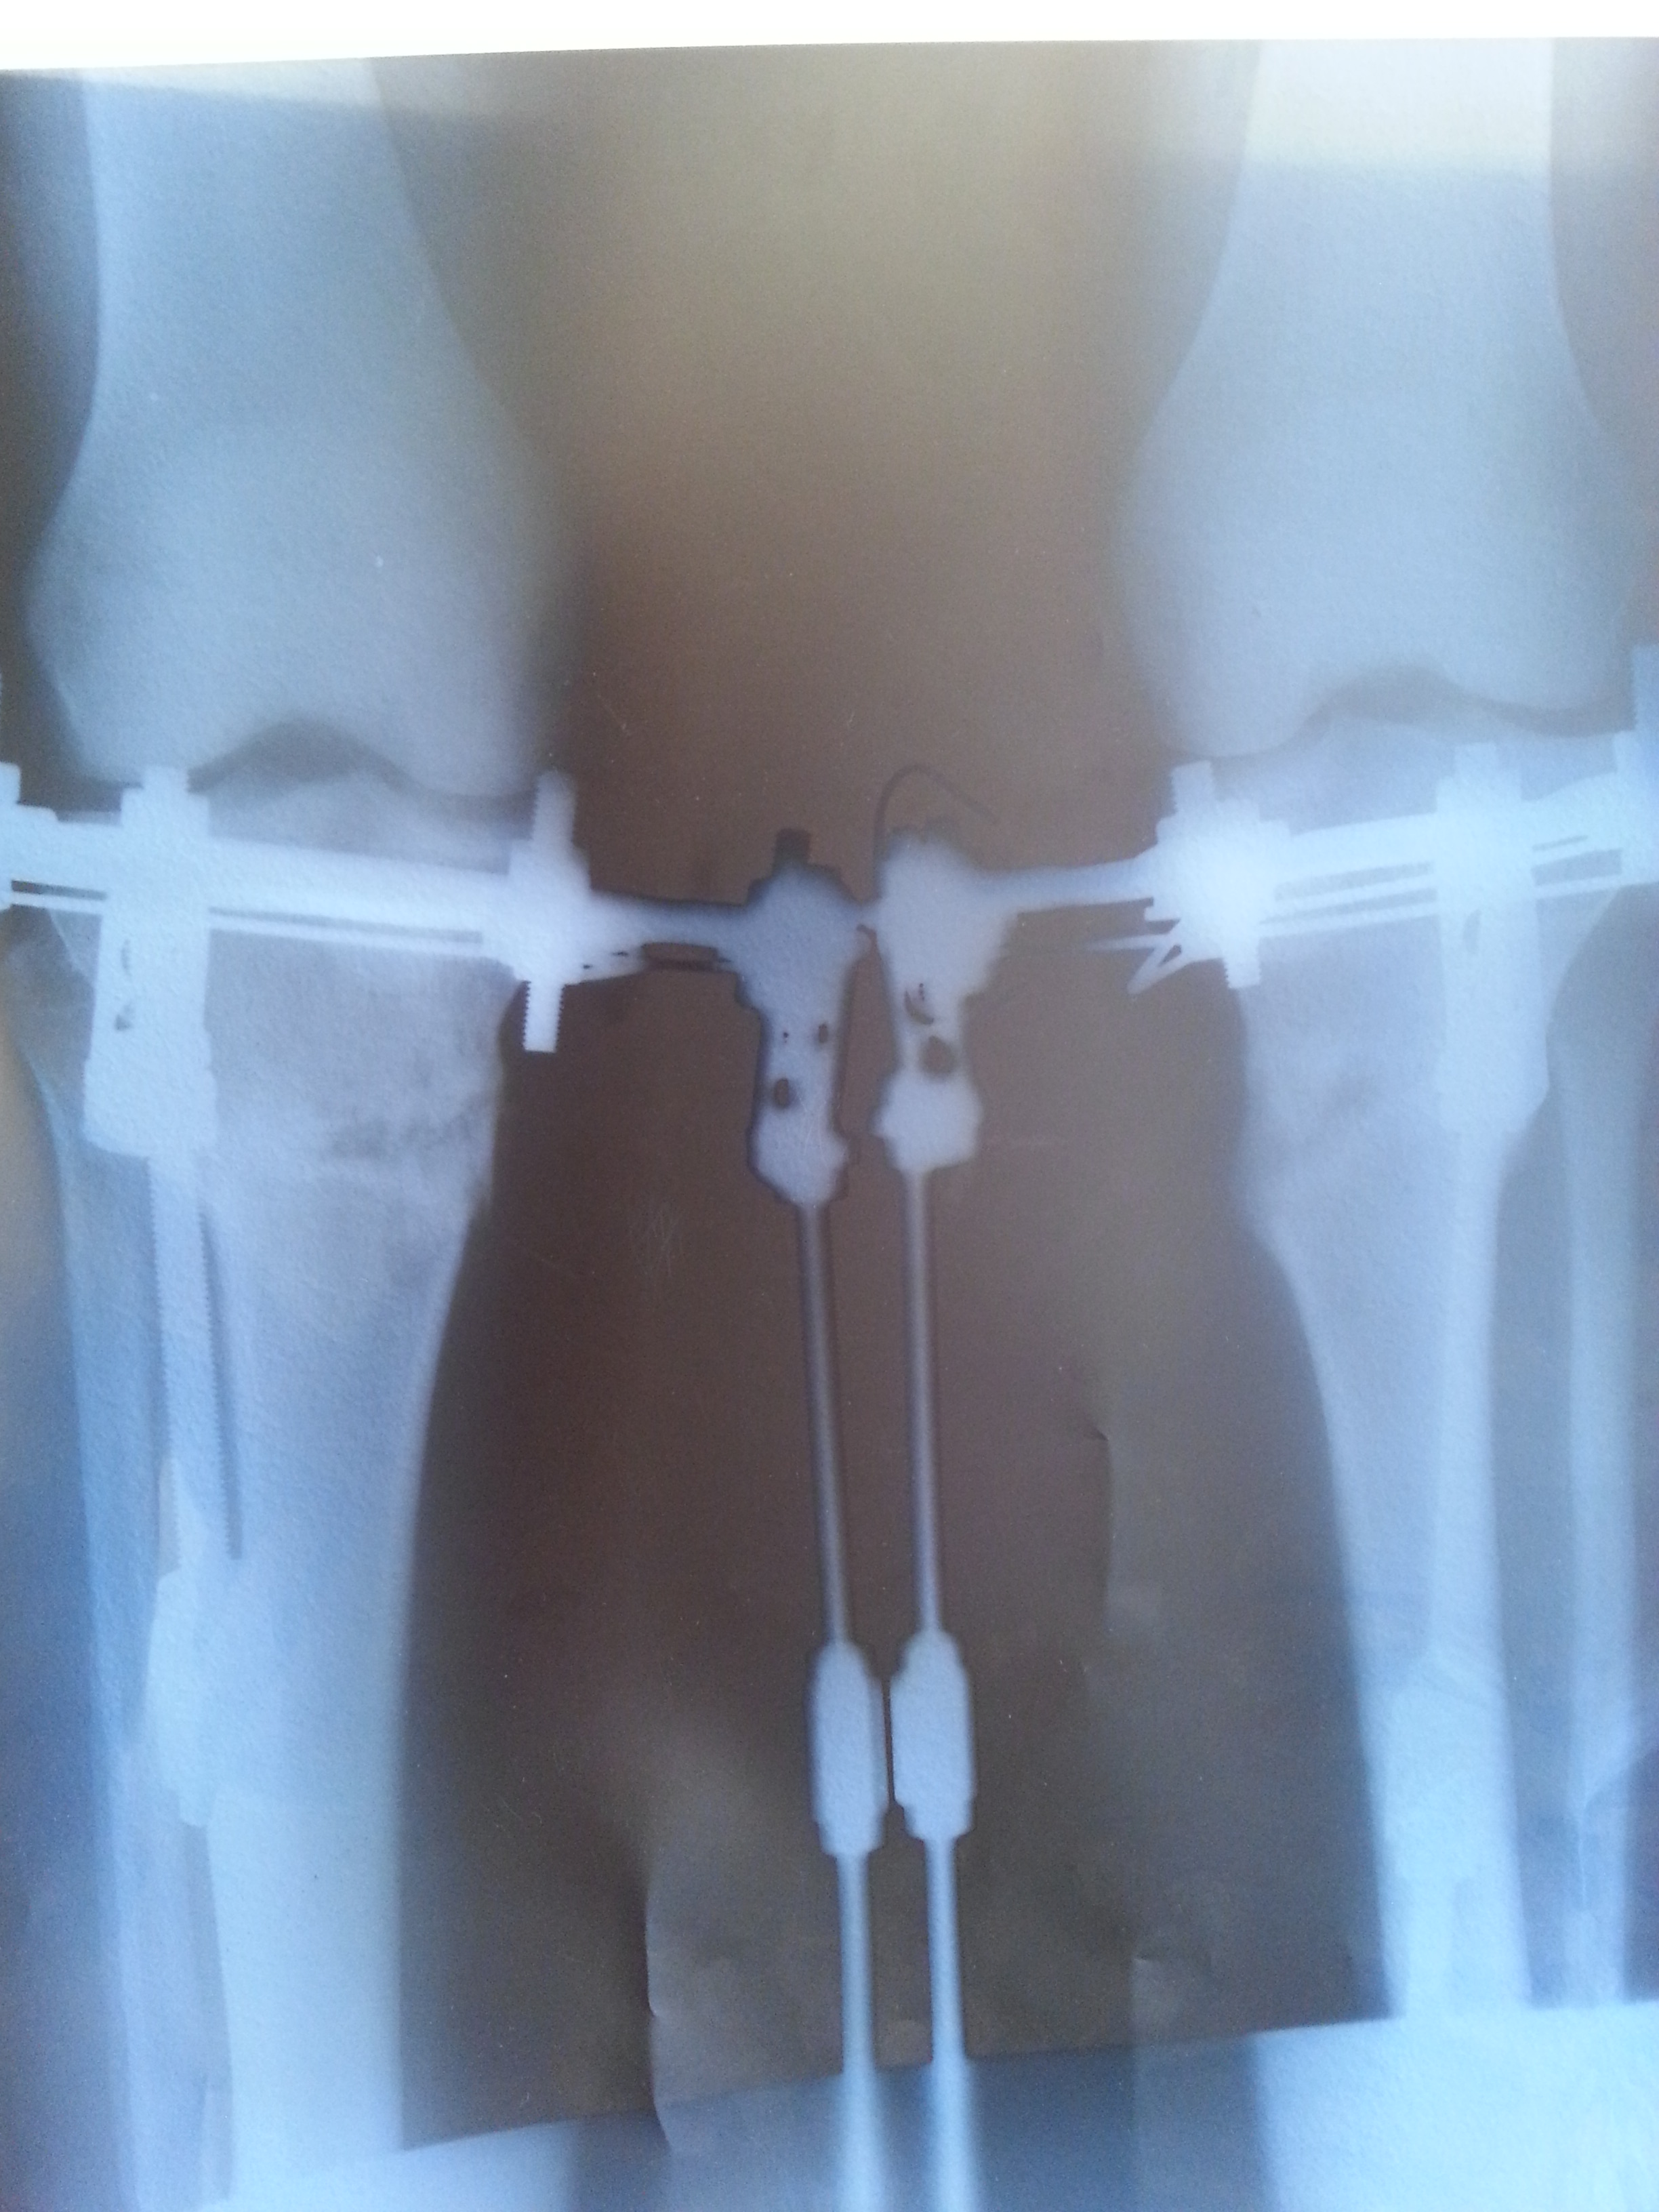

Рентген снимки 102 дня с момента операции.

Дата операции 15.03.2014г.

Дата снятия аппаратов 15.08.2014г.

Срок лечения 5 месяцев.